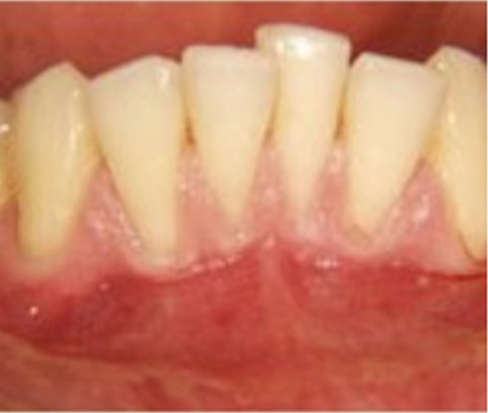

2. Pinhole® Surgical Technique (PST™): PST™ is a minimally invasive alternative to traditional gum grafting. This technique involves creating a small pinhole in the gum tissue and using specialized instruments to gently reposition the gum tissue over the exposed roots. PST™ offers faster recovery times and minimal discomfort compared to traditional grafting methods.